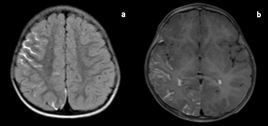

Figure 3 Pericallosal lipoma with bilateral parieto-occipital polymicrogyria.

T1-weighted (a) and T2-weighted (b) axial images showing midline hyperintense lesion (red arrow) extending into choroid plexus of bilateral lateral ventricles with thin peripheral hypointense rim (white arrow). Mild white matter volume loss with polymicrogyria in bilateral parieto-occipital lobes (black arrows). T1-SPIR sagittal image (c) showing signal suppression of the lesion (red arrow) with hypointense peripheral rim (white arrow). Axial FFE image (d) shows irregular central and peripheral blooming due to chemical shift artefact.

SPIR, spectral presaturation with inversion recovery; FFE, fast field echo.